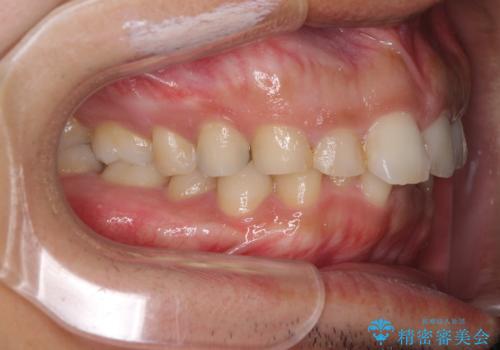

- 深い咬み合わせと前歯のデコボコ、奥歯の欠損を気にして来院された患者様です。

歯列矯正はインビザラインを使用し、矯正治療中の適切な時期に奥歯の欠損部位にインプラントを埋入することとしました。